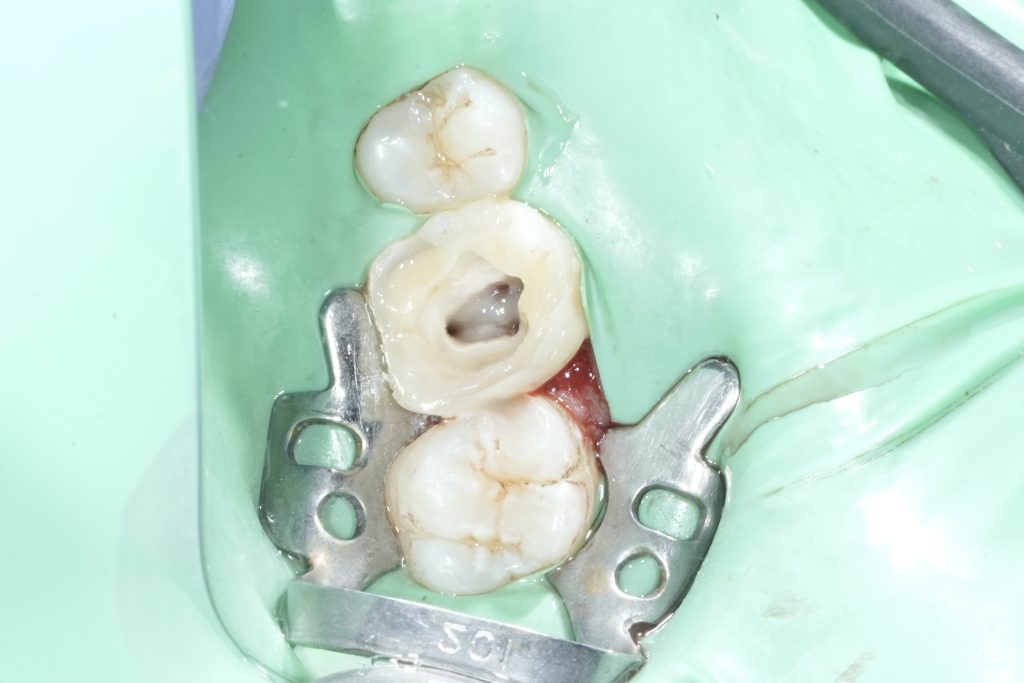

Immediate Dentin Protection

After obturation, the pulp chamber floor and canal orifices were sealed to prevent microleakage. The chamber was cleaned thoroughly to remove sealer remnants and debris, ensuring optimal bonding conditions.

Cavity Design for Biomimetic Overlay

The cavity was refined into a butt-joint style preparation. Unsupported enamel was removed, while sound enamel margins were preserved. Cuspal reduction was selectively performed only where indicated, guided by crack presence and remaining wall thickness.

This design allowed stress distribution over a larger bonded surface area while avoiding unnecessary tooth reduction.

Adhesive Protocol

Selective enamel etching was performed, followed by application of a dentin bonding agent according to manufacturer instructions. The adhesive protocol focused on achieving a durable hybrid layer and minimizing polymerization stress.